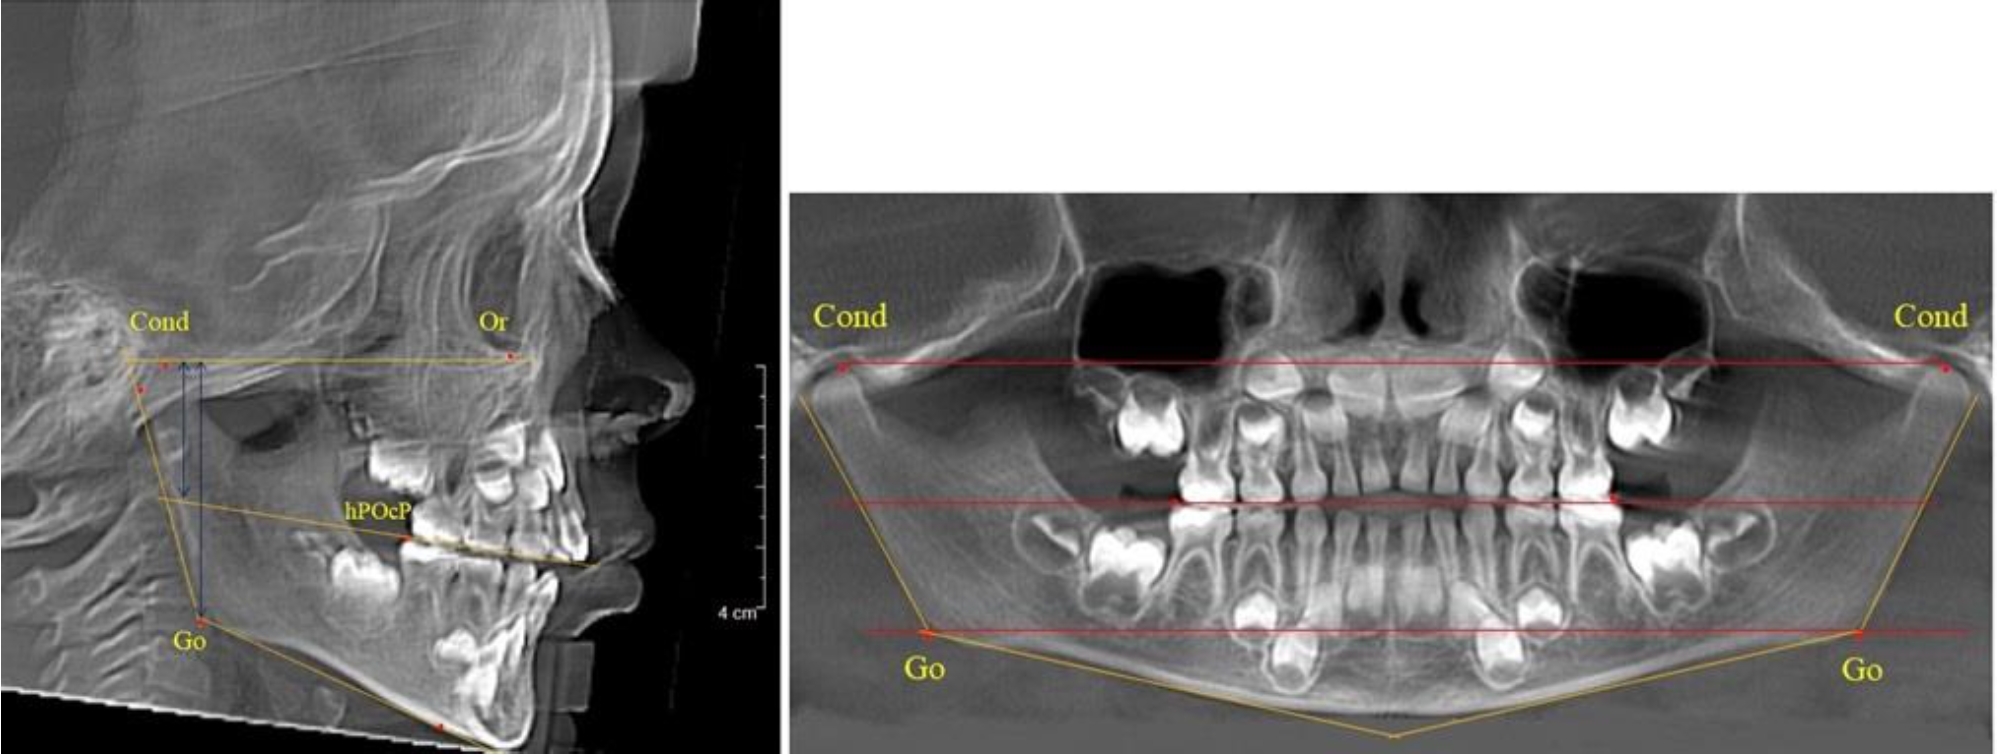

В 3-й группе были проанализированы 9 телерентгенограмм и 9 ортопантомограмм, что составило (8,49 ± 2,71) % от числа изученных рентгенограмм (рис. 3).

Рис. 3. ТРГ и ОПТГ пациента после смены молочных резцов

На всех рентгенограммах произошла смена молочных резцов постоянными. Окклюзионная линия делила ветвь на два отдела.

Высота ветви у детей у детей 3-й группы составляла (51,07 ± 2,72) мм, что было достоверно больше, чем у детей 1-й группы (р ˂ 0,05). При этом высота верхней окклюзионно-суставной части была (29,06 ± 1,44) мм, а нижней – (22,01 ± 1,59) мм. Высота верхней части была больше нижней, что и определяло особенности соразмерности частей ветви нижней челюсти в анализируемый возрастной период.

Относительные показатели соразмерности частей ветви нижней челюсти показали, что отношение высоты верхней части ветви к нижней в среднем составляло 1,32 ± 0,14. Отношение общей высоты ветви к верхней ее части составляло 1,75 ± 0,12, а отношение общей высоты ветви к нижней ее части было 2,32 ± 0,17, что и определяло особенности соразмерности частей ветви нижней челюсти в анализируемый возрастной период.

В 4-й группе были проанализированы 12 комплектов рентгенограмм, что составило (11,32 ± 3,08) % от общего числа. На всех рентгенограммах произошла полная смена всех молочных зубов постоянными. Окклюзионная линия делила ветвь на два отдела (рис. 4).

Рис. 4. ТРГ пациента после смены всех молочных резцов

Высота ветви у детей 4-й группы составляла (54,27 ± 2,59) мм, что было достоверно больше, чем у детей 1-й группы (р ˂ 0,05). При этом высота верхней окклюзионно-суставной части была (32,51 ± 1,72) мм, а нижней – (21,76 ± 1,42) мм. Высота верхней части была больше нижней, что и определяло особенности соразмерности частей ветви нижней челюсти в анализируемый возрастной период.

Относительные показатели соразмерности частей ветви нижней челюсти показали, что отношение высоты верхней части ветви к нижней в среднем составляло 1,49 ± 0,12. Отношение общей высоты ветви к верхней ее части составляло 1,67 ± 0,14, а отношение общей высоты ветви к нижней ее части было 2,49 ± 0,15, что и определяло особенности соразмерности частей ветви нижней челюсти в анализируемый возрастной период.

В 5-й группе были проанализированы 14 комплектов рентгенограмм, что составило (13,21 ± 3,29) % от общего числа. На всех рентгенограммах отмечен очередной этап подъема высоты прикуса, обусловленный прорезыванием вторых постоянных моляров. Окклюзионная линия делила ветвь на два отдела (рис. 5).

Рис. 5. ТРГ и ОПТГ пациента после смены молочных зубов и прорезывания вторых постоянных моляров